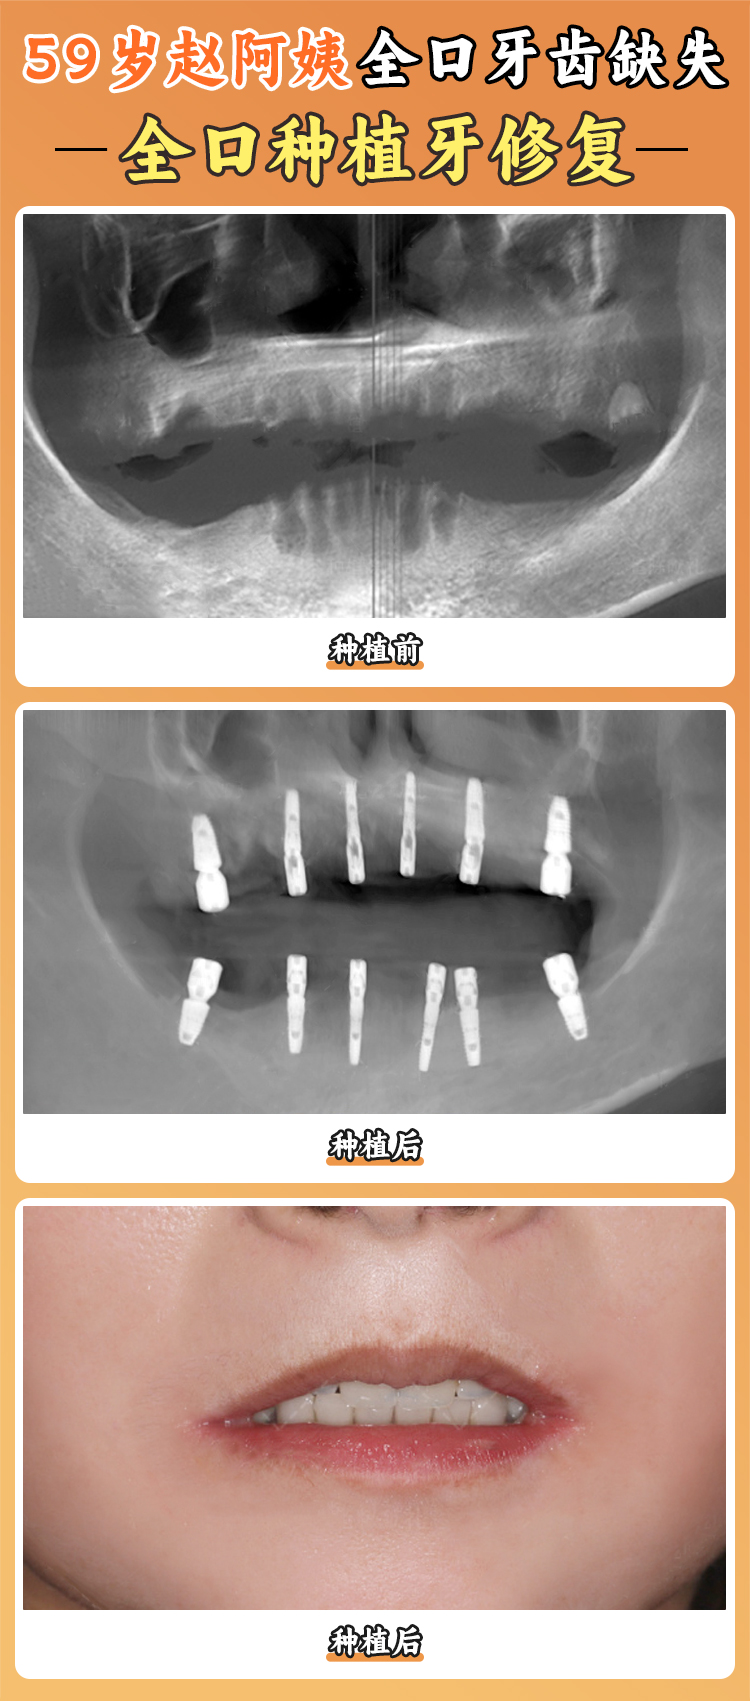

半口和全口種植牙價(jià)格:半口種植牙價(jià)格根據(jù)種植方式和使用的種植體不同有所差異,一般在6 - 10萬元起;全口種植牙價(jià)格在12 - 20萬元起。例如上??堤┌莶┛谇会t(yī)院全口種植牙價(jià)格10 - 20萬元起,半口種植牙價(jià)格6 - 10萬元起。

有特別多患者在泰康拜博口腔醫(yī)院得到了良好的治療成效。例如有一位患者牙齒重度缺失,在深圳泰康拜博口腔華強(qiáng)北總院接受了4顆種植體支撐全口修復(fù),總花費(fèi)4.8萬(比私立機(jī)構(gòu)省3萬),術(shù)后當(dāng)天就能吃腸粉,咬花生也沒問題。還有一位地包天患者,在泰康拜博口腔醫(yī)院進(jìn)行牙齒矯正手術(shù),術(shù)后牙齒變得非常整齊,地包天問題也得到了良好的改善。